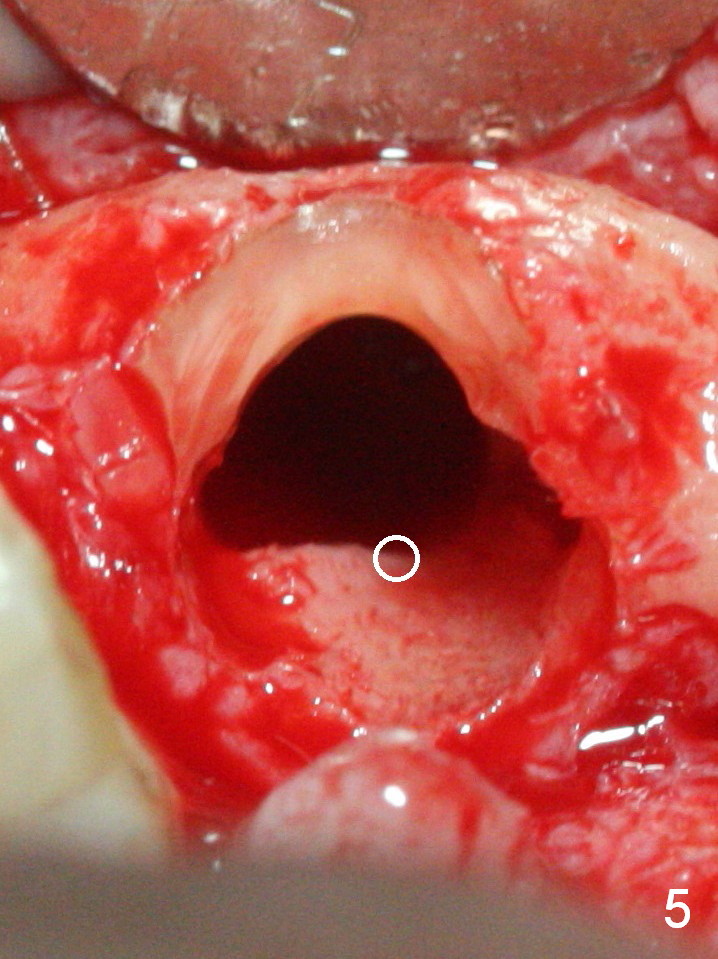

When the bridge is sectioned between #7 and 8, the tooth #6 is found non-salvageable (Fig.1). Incision shows the atrophic buccal plate at #7 (Fig.2 arrowheads); to prevent the same feature from happening at #6 with thin buccal plate, the most buccal portion of the root is preserved (socket shield (Fig.2-4: *)). The initial osteotomy is established in the palatal slope at #6 (Fig.5 circle) with 1.5 mm drill (Fig.6,7). A portion of the root is visible in Fig.6 (arrowheads). After sequential osteotomy with 2 mm, 3 mm (Fig.8) and 3.2 mm drills, a 4x15 mm implant is placed (Fig.10). To accommodate the cross bite, the coronal portion of the implant (Fig.9 white circle) is positioned close to the socket shield. It appears that the shield prevents the implant from encroaching the buccal plate.